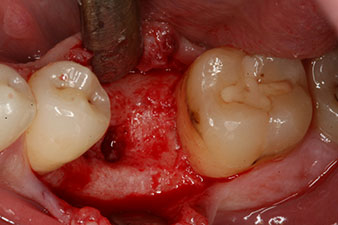

Шест седмици след екстракцията се открива непълна осификация след препарацията на мукопериосталното ламбо в областта на предходната алвеола мезиално.

Имплантът е поставен както е планирано след цялостно отстраняване на гранулационната тъкан (blueSky, bredent).

Тези стойности могат да показват отворено лечение или дори имедиатно възстановяване. Поради недостатъчния обем на кресталната кост при импланта, областта е подсилена с костните частици, събрани по време на препарацията на имплантното ложе и зашити, за да се изолира слюнката.